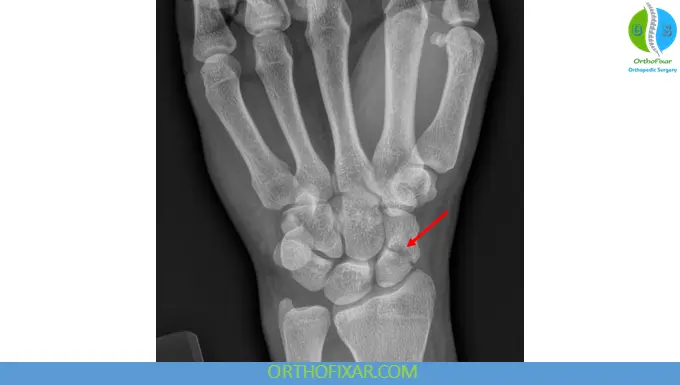

Imaging and Diagnosis

Standard radiographs include:

- PA view in ulnar deviation

- Lateral view

- Oblique and clenched fist views

However, up to 25% of initial X-rays may be negative.